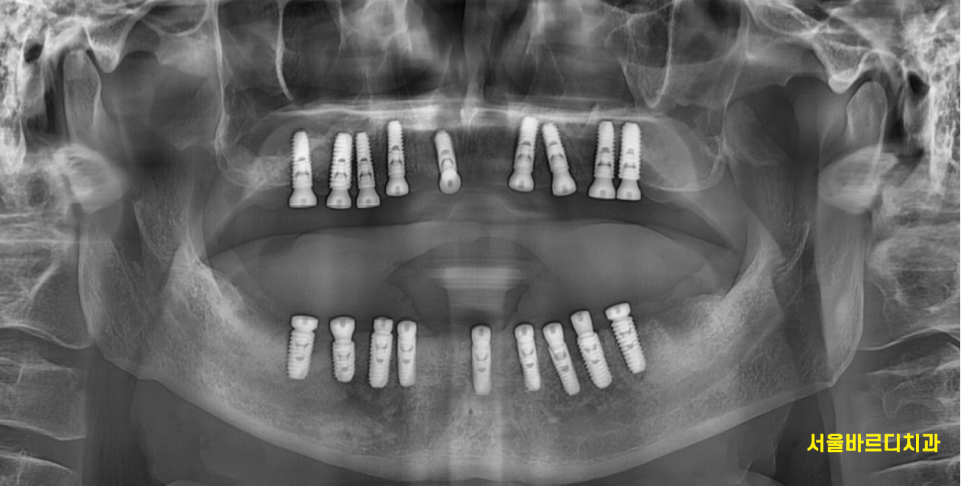

240904

짜잔~~

치료가 끝난 모습입니다.

약 9개월동안 치료를 진행하였네요.

1년은 안걸렸지만

계절이 3번이 바뀔동안

치과를 몇번이나 와주시고

약속 한번 어기지 않은 환자분께 감사함을 표합니다.